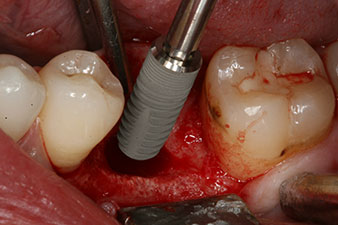

Das Drehmoment beim maschinellen Einbringen war 43 Ncm. Zusätzlich wurde, nach Einschrauben eines speziellen, auf das Implantatsystem abgestimmten Mess-Pfostens (SmartPeg), der ISQ-Wert mit der Sonde des W&H Osstell ISQ Modul bestimmt.

Dieses Modul ist für das Implantmed von W&H optional erhältlich und wird an den Implantologiemotor gedockt (vgl. Abb. 11). Der dimensionslose ISQ-Wert war direkt bei der Insertion 64 in oro-vestibulärer und 68 in mesio-distaler Richtung (Maximalwert = 100). Dies hätte eine offene Einheilung oder sogar Sofortversorgung erlaubt.